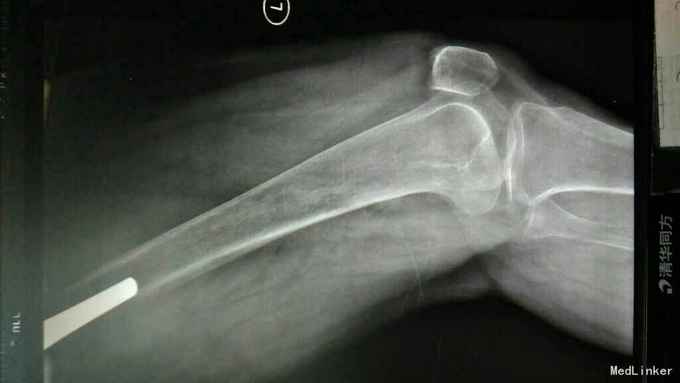

主诉:左髋关节置换术后疼痛活动受限3年 病史:3年前患者因左股骨颈骨折在当地县医院就诊,诊断明确后行全髋关节置换术,术前正常出院。出院后即感左髋关节疼痛不适,活动疼痛加重,休息缓解,疼痛位于腹股沟明显。反复于当地医院及成都等医院就诊,诊断不明确,考虑有金属过敏可能。4天前患者疼痛加重,活动进一步受限,无关节红肿,无肿胀,无畏寒发热,无其他关节疼痛。为进一步治疗收入我科。 患病以来。精神食欲可,体力下降。

查体:轮椅推入,左髋关节后外侧见10cm手术切口瘢痕,双侧腹股沟压痛,双侧大转子叩痛,双髋关节活动受限,4字实验(+),双下肢肌力3级。左乱关节屈曲90度,旋转不能。左下肢纵向叩痛(+)。 辅助检查:彩超示脂肪肝。x线腰椎骨质疏松,压缩性骨折。ESR 38,CRP 12。 影像学如下:

诊断:左髋关节置换术后假体松动; 右侧股骨头缺血坏死; 重度骨质疏松症 高血压病 压缩性骨折 治疗:左髋关节翻修术。(植骨、钛网骨水泥杯,骨水泥柄或翻修长柄MP(Link))